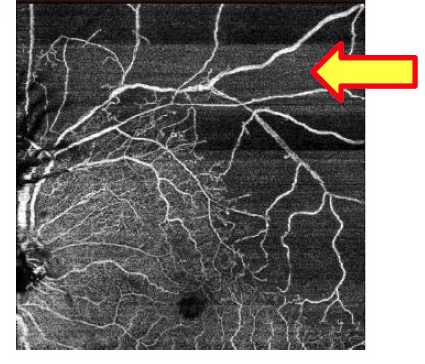

スウェプトソースOCT DRI OCT TRITON(OCTアンギオグラフィー)

OCTAngiograrhyは、造影剤を用いることなく、OCT撮影するだけで網膜・脈絡膜血管内の血液の様子を可視化することのできる新しい技術です。